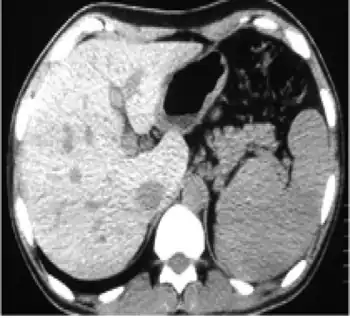

| In non-contrast abdominal computed tomography, increased density of liver compared with spleen was reported | |